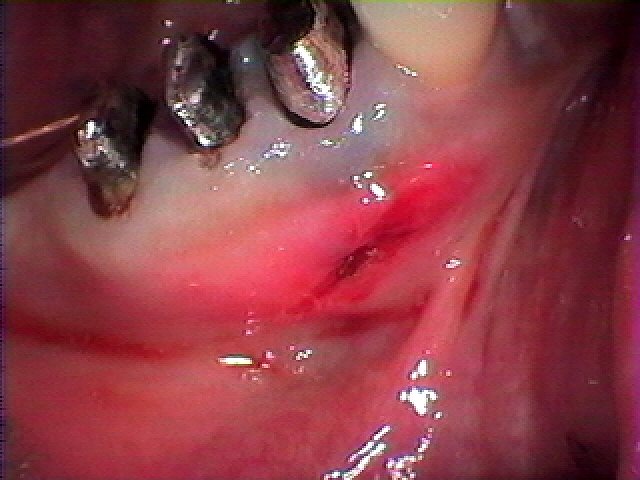

こんな位置が腫れていました